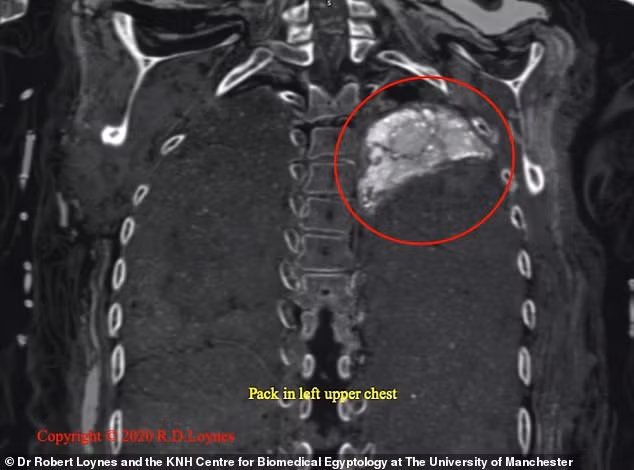

Takabut qua đời khi khoảng 20 tuổi bởi một vết đâm ở sau lưng gần vai trái. Vào năm 1834, xác ướp Takabut được đưa đến Ireland.